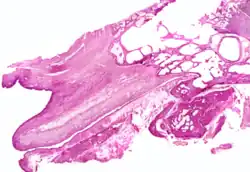

The position and relations of the pharyngeal opening are described with the nasal part of the pharynx. The mucous membrane of the tube is continuous in front with that of the nasal part of the pharynx, and behind with that of the tympanic cavity; it is covered with ciliated pseudostratified columnar epithelia and is thin in the osseous portion, while in the cartilaginous portion it contains many mucous glands and near the pharyngeal orifice a considerable amount of adenoid tissue, which has been named by Gerlach the tube tonsil.